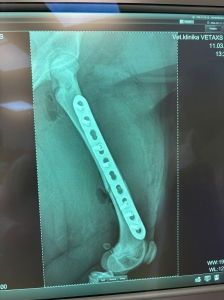

Včera sme prijali toto zranené šteniatko. Fenka zostala na pozorovanie na veterine a zistili že má zlomenú stehennú kosť :(

TERMÍN OPERÁCIE JE ZAJTRA 12:00 U PÁNA DOKTORA ADAMAŤA V TRENČÍNE

DOLORES má po operácii ♥. Ďakujeme všetkým za pomoc ♥♥♥. Držte malej palce aby bola čoskoro fit :)